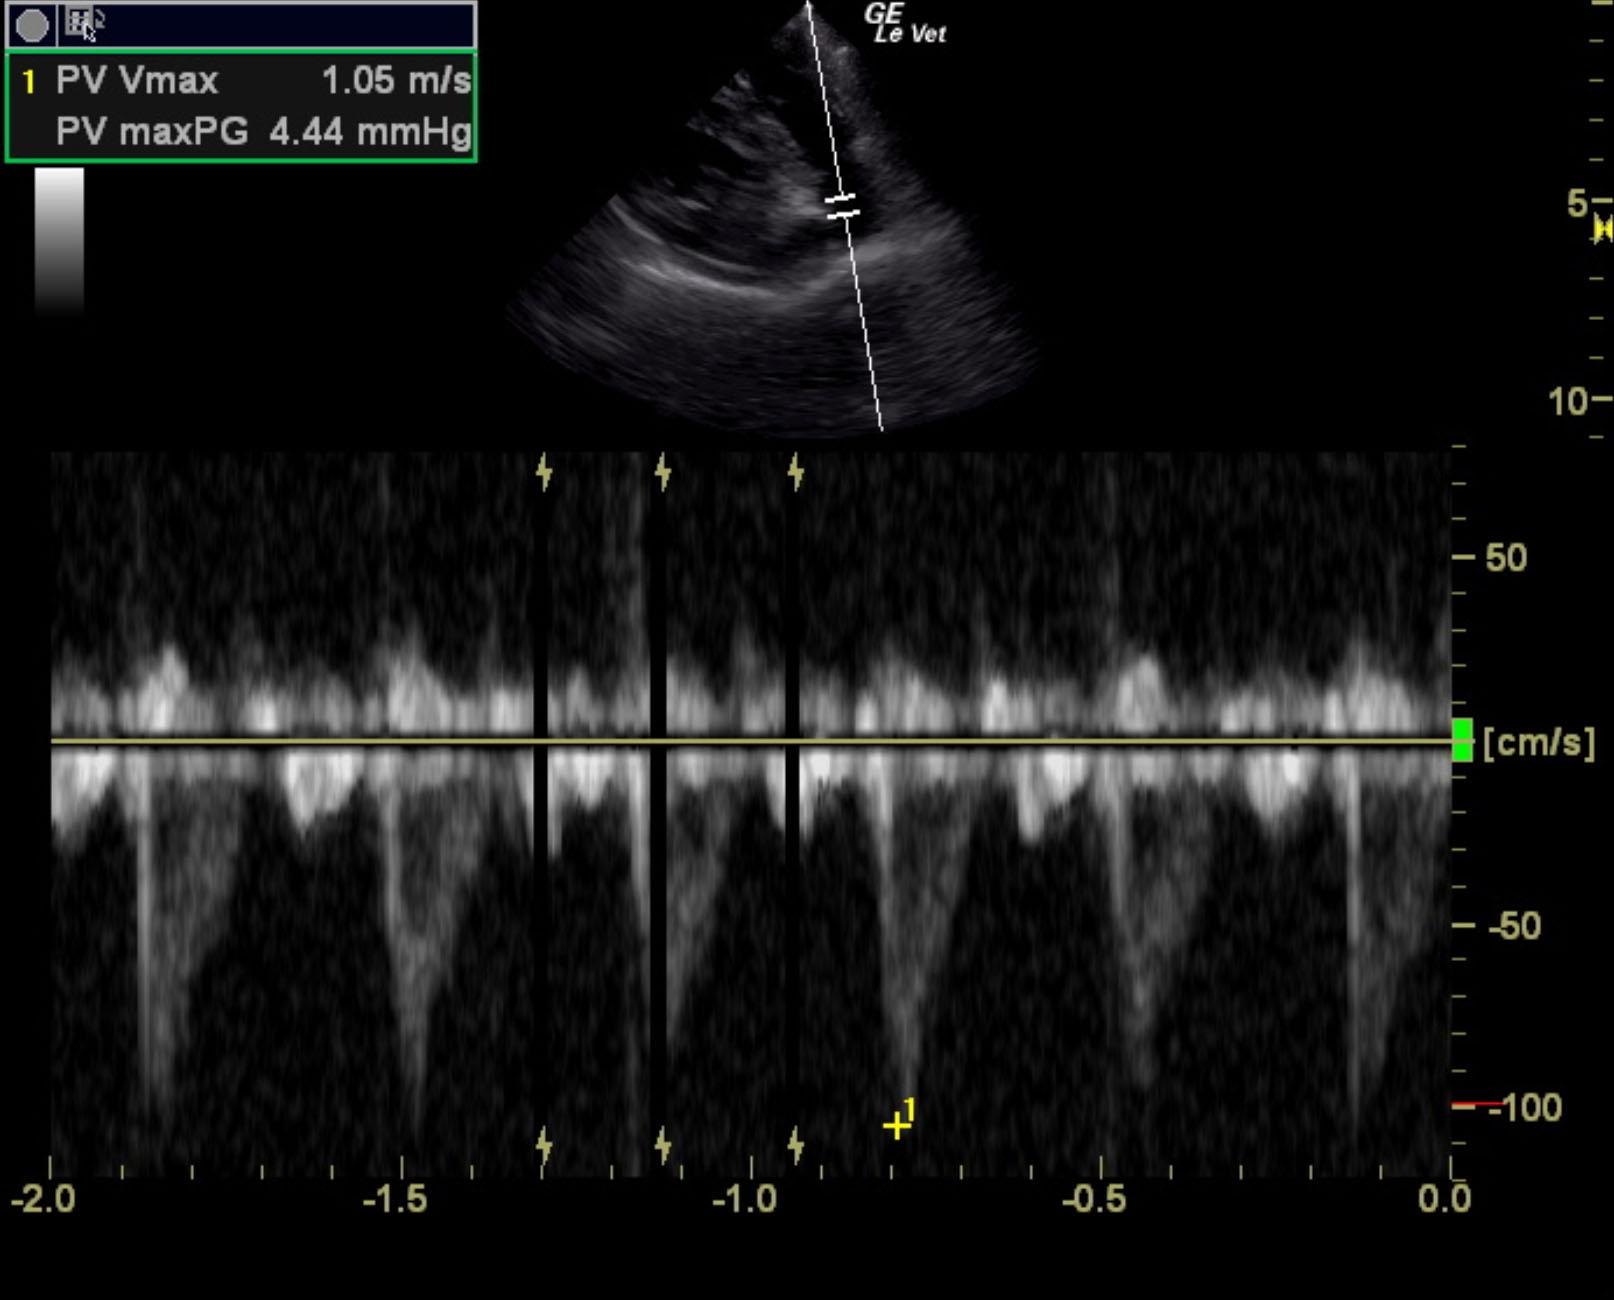

The cardiac presentation revealed moderate left and right sided overload with tricuspid and mitral valve vegetative lesions. Left atrial and right atrial enlargement was noted. Right ventricular overload was noted with flattening of the ventricular septum. Slight prolapse of the anterior mitral valve leaflet was noted. Prolapse of the tricuspid vavle was also noted. Significant pulmonic insufficiency and tricuspid insufficiency was noted. This is consistent with pulmonary hypertension.

Pulmonic insufficiency velocity 1.8 m.sec.

Tricuspid insufficiency velocity 3.9 m/sec